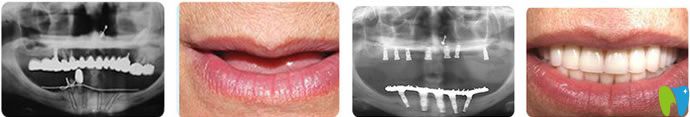

深圳鵬程口腔秉承導(dǎo)入高新口腔診療技術(shù),如,即刻負(fù)重技術(shù)、微創(chuàng)種植技術(shù)、3天牙齒美容修復(fù)、隱形矯正等技術(shù)水平廣受好評(píng)。